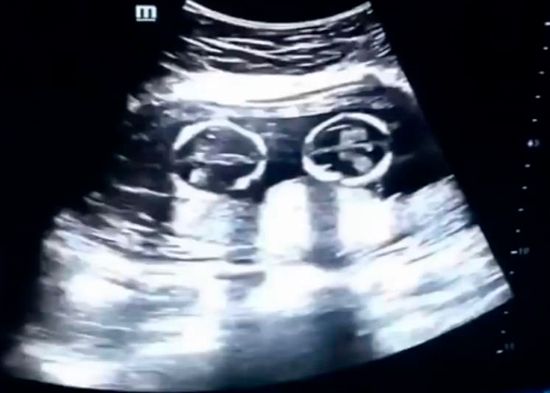

Una ecografía capta la 'pelea' entre dos gemelas en el vientre de su madre

REDACCIÓN INTERNACIONAL.- El video de una ecografía realizada en Yinchuan (Ningxia, China) en la que se ve a dos hermanas gemelas ‘peleándose’ dentro del vientre de su madre, se ha vuelto viral desde que este lunes apareciera en las redes sociales.

En la grabación, realizada por el padre el pasado mes de diciembre, se observa la pugna de los fetos, de tan solo cuatro meses, que parecen sacudirse patadas y puñetazos.

Se trata de un extraño tipo de embarazo de riesgo en el que las gemelas comparten saco amniótico y placenta dentro del útero. Las dos nacieron sanas el pasado 8 de abril mediante cesárea.